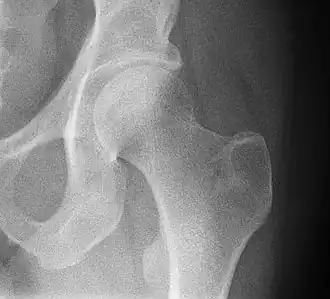

![]() Рентгенограмма тазобедренного сустава. | |

Та́зобе́дренный суста́в (лат. articulatio coxae) — чашеобразный, многоосный сустав, образованный полулунной поверхностью вертлужной впадины тазовой кости и суставной поверхностью головки бедренной кости. Вертлужная губа, сращённая с краем вертлужной впадины, углубляет последнюю.

Суставная капсула к тазовой кости прикрепляется по окружности вертлужной впадины, оставляя вертлужную губу внутри полости сустава. К бедренной кости капсула прикрепляется спереди вдоль межвертельной линии, сзади — немного отступая кнутри от межвертельного гребня. Таким образом, шейка бедра располагается в суставной полости.